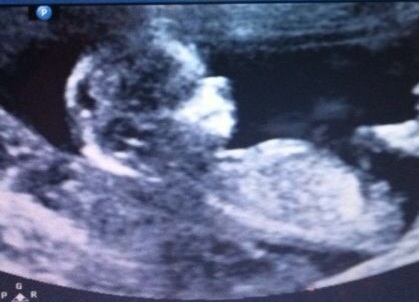

Is there something vissible at one of these scans? It was taken at 13+4 weeks. I will really appriciate your guess! Can you also say why you are thinking boy or girl?

I say boy based off second pic...nub is angled up.

Going off the 3rd pic, Im going with Pink Bundle!

50/50 so far.. Is it possible for a boy to have a forked nub?